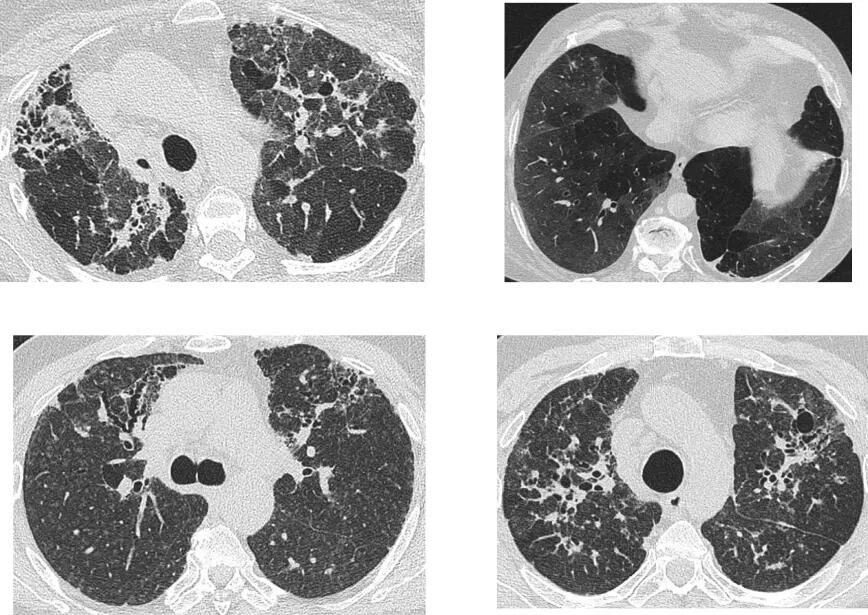

Фиброз кт